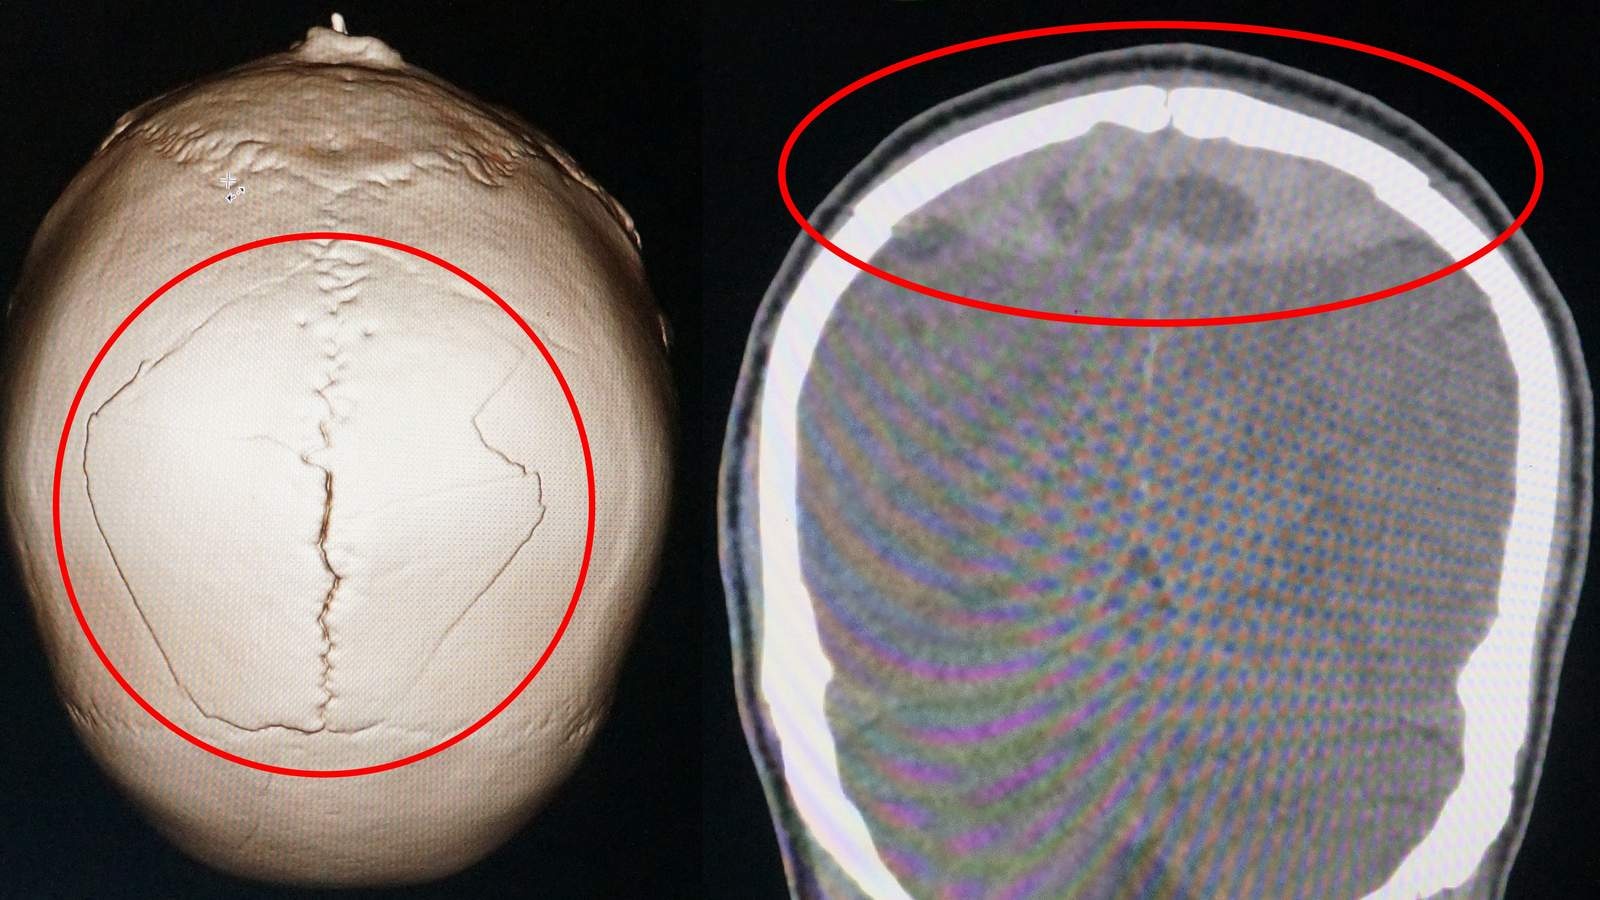

Ông Chiến bị công an bắt lúc sức khỏe bình thường nhưng chỉ một ngày sau ông này phải nhập viện trong tình trạng chấn thương sọ não.